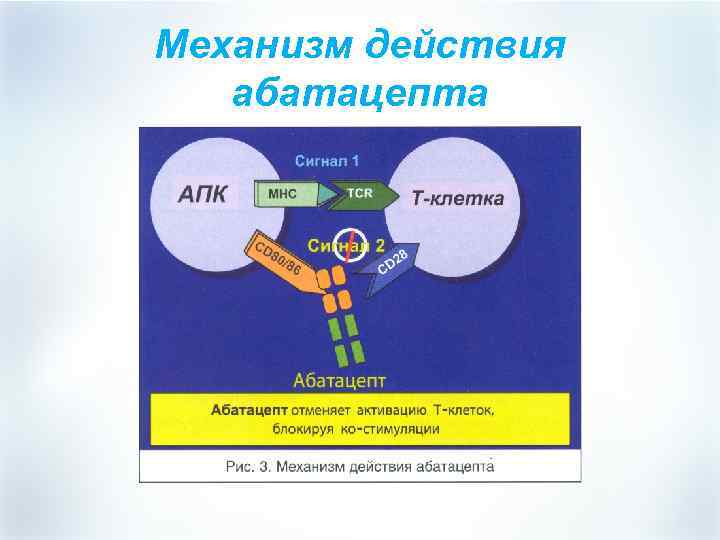

Механизм действия абатацепта

Механизм действия абатацепта

Роль CTLAg § При наличии обоих сигналов Т-лимфоциты подвергаются пролиферции и синтезируют цитокины, которые активируют друге клетки иммунной системы, в первую очередь макрофаги. При отсутствии «костимуляторного» сигнала Т-лимфоциты теряют способность эффективно отвечать на антигенные стимулы и подвергаются апоптозу. Наиболее мощным физиологическим ингибитором взаимодействия CD 28 -CD 80CD 86 является CTLA 4 (cytotoxic T-lymphocyte-associated antigen 4) – рецептор для CD 80CD 86, который экспрессируется после активации АПК и взаимодействует с этими лигандами с более высокой авидностью (примерно в 500 -2500 раз выше), чем CD 28. Эта молекула рассматривается как негативный регуляторный рецептор, который ограничивает неконтролируемую активацию Т-клеток, в процессе иммунного ответа.

Роль CTLAg § При наличии обоих сигналов Т-лимфоциты подвергаются пролиферции и синтезируют цитокины, которые активируют друге клетки иммунной системы, в первую очередь макрофаги. При отсутствии «костимуляторного» сигнала Т-лимфоциты теряют способность эффективно отвечать на антигенные стимулы и подвергаются апоптозу. Наиболее мощным физиологическим ингибитором взаимодействия CD 28 -CD 80CD 86 является CTLA 4 (cytotoxic T-lymphocyte-associated antigen 4) – рецептор для CD 80CD 86, который экспрессируется после активации АПК и взаимодействует с этими лигандами с более высокой авидностью (примерно в 500 -2500 раз выше), чем CD 28. Эта молекула рассматривается как негативный регуляторный рецептор, который ограничивает неконтролируемую активацию Т-клеток, в процессе иммунного ответа.